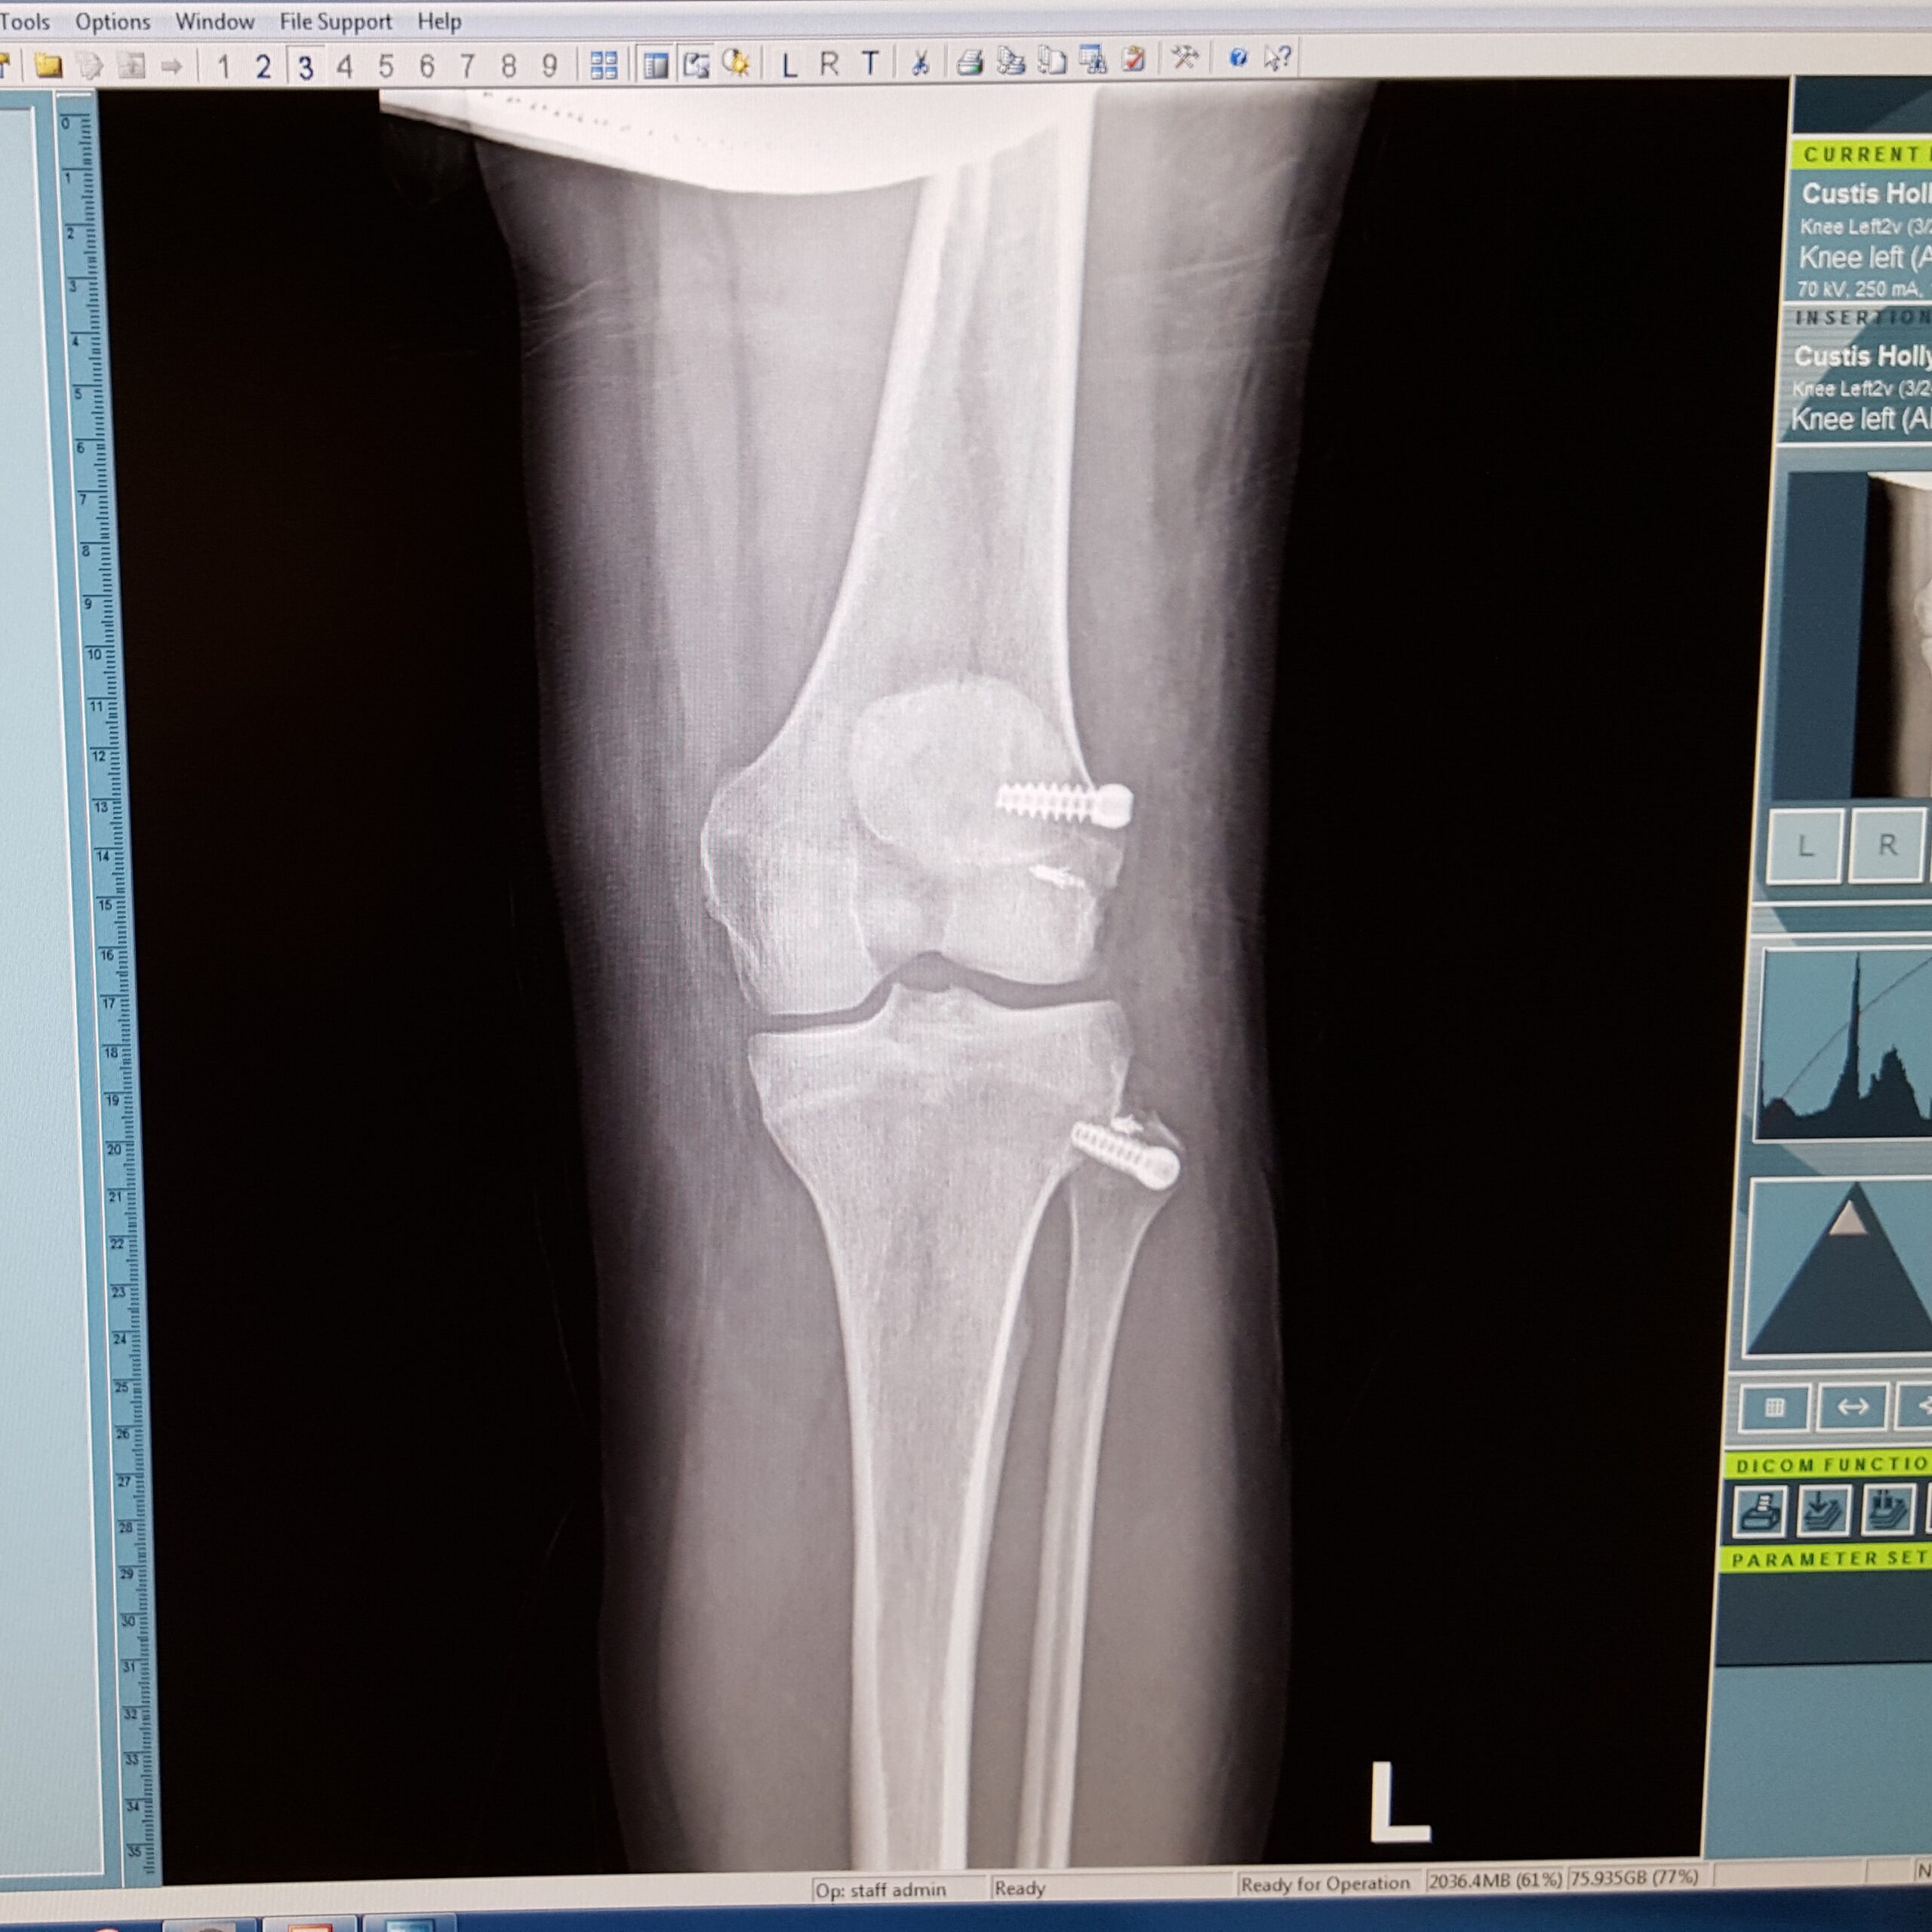

They then wheeled me over to the xray room and took a couple of xrays. You can clearly see the screws in my leg where they were grafting and fixing the fracture which is fascinating. I asked if this meant I would be stopped at airport security. They replied that it depends on the material they used in surgery but likely not. I thought darn, I’m already picked a lot for extra security, it would be nice to have a built in excuse. Oh, well.